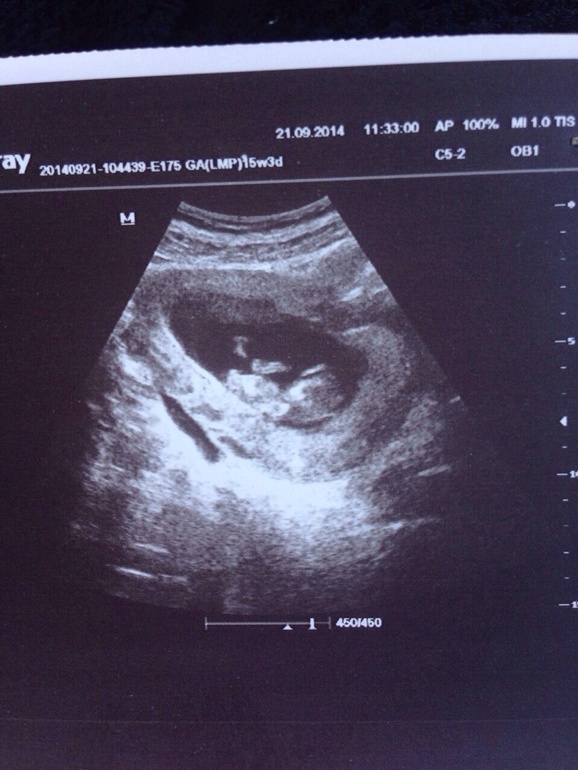

Вчера были на узи))) срок 11 недель)ходили с папой) ножками и ручками машем) такой человечек))) в общем эмоций куча!))ну и фото на память

Сказали мальчик))) сами оба очень хотим сына))) такое эмоциональное узи было для нас с мужем))) но маленькие мы ) всего 42 мм, для скрининга сказали недельку подождать! Ногами так размахивал и руками что врач сказал что активность прям +++))) мотька, спасибо тебе огромное, человеческое!!